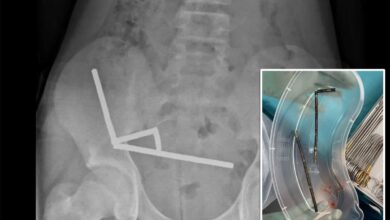

Dále viděli dětského psychiatra, o kterém tvrdí, že předepsal Sanaa mocný antipsychotický risperdal.

„Asi po týdnu, kdy byla na tom, jsme to začali zkoumat online. A tehdy jsem řekl, že tento lék by neměl být nikomu dán nikomu, pokud to není 13.“

Sanaa však zažila to, co Lisa věřila, že jsou vedlejší účinky léku, a 36 hodin předtím, než byla Sanaa spěchána do pohotovostní místnosti, Lisa tvrdí, že nazvala psychiatr. Bylo jí údajně řečeno, že zavolá zpět, ale ne.